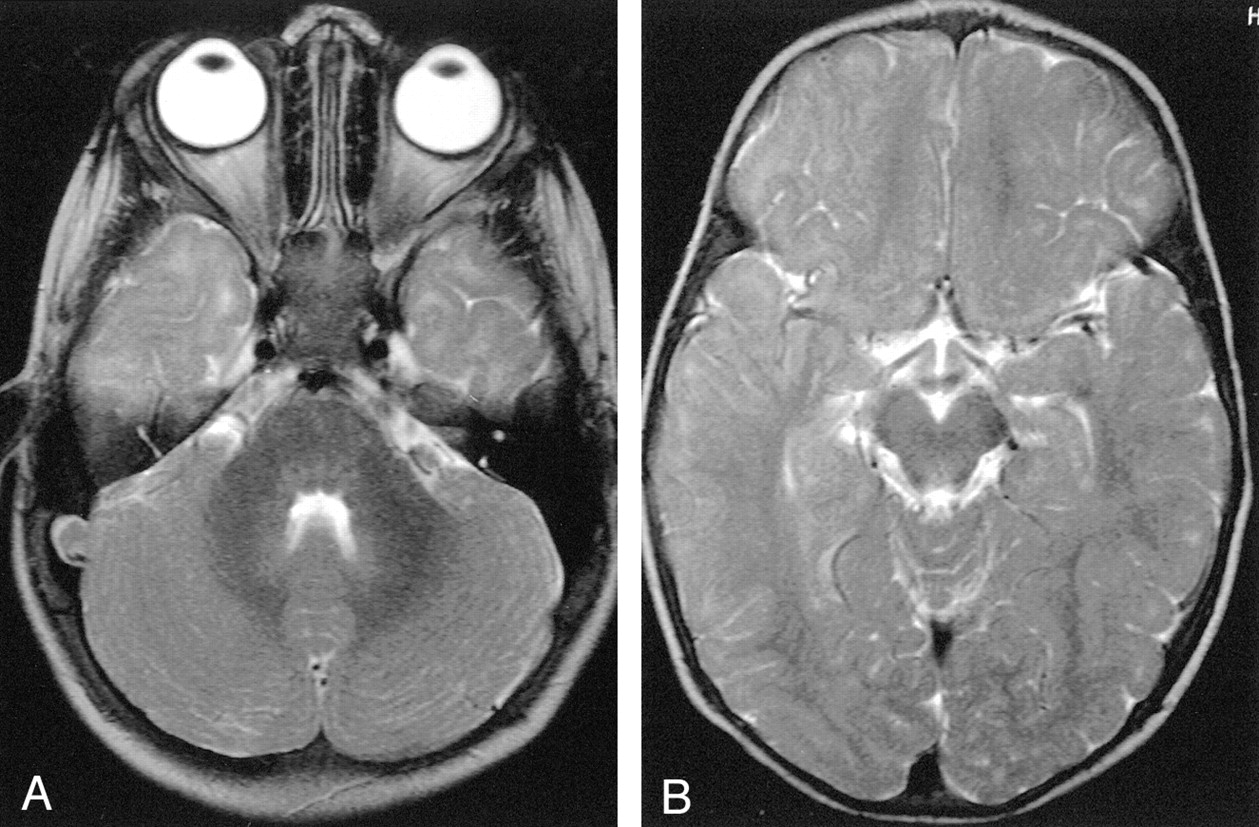

Axial T2-weighted MR images.

A, Image in a 21-month-old girl with grade 0 myelination in the frontal lobe. The subcortical white matter is clearly hyperintense, so not myelinated, in the prerolandic area and along the first and second convolutions bilaterally. Subcortical hyperintensity was also evident in the frontopolar regions.

B, Example of grade 2 myelination in the frontal area. A T2 hyperintensity is present along the first and second convolutions, while the prerolandic area is myelinated.

C, Example of grade 3 myelination. T2 hyperintensity is no longer evident, and myelination appears complete.